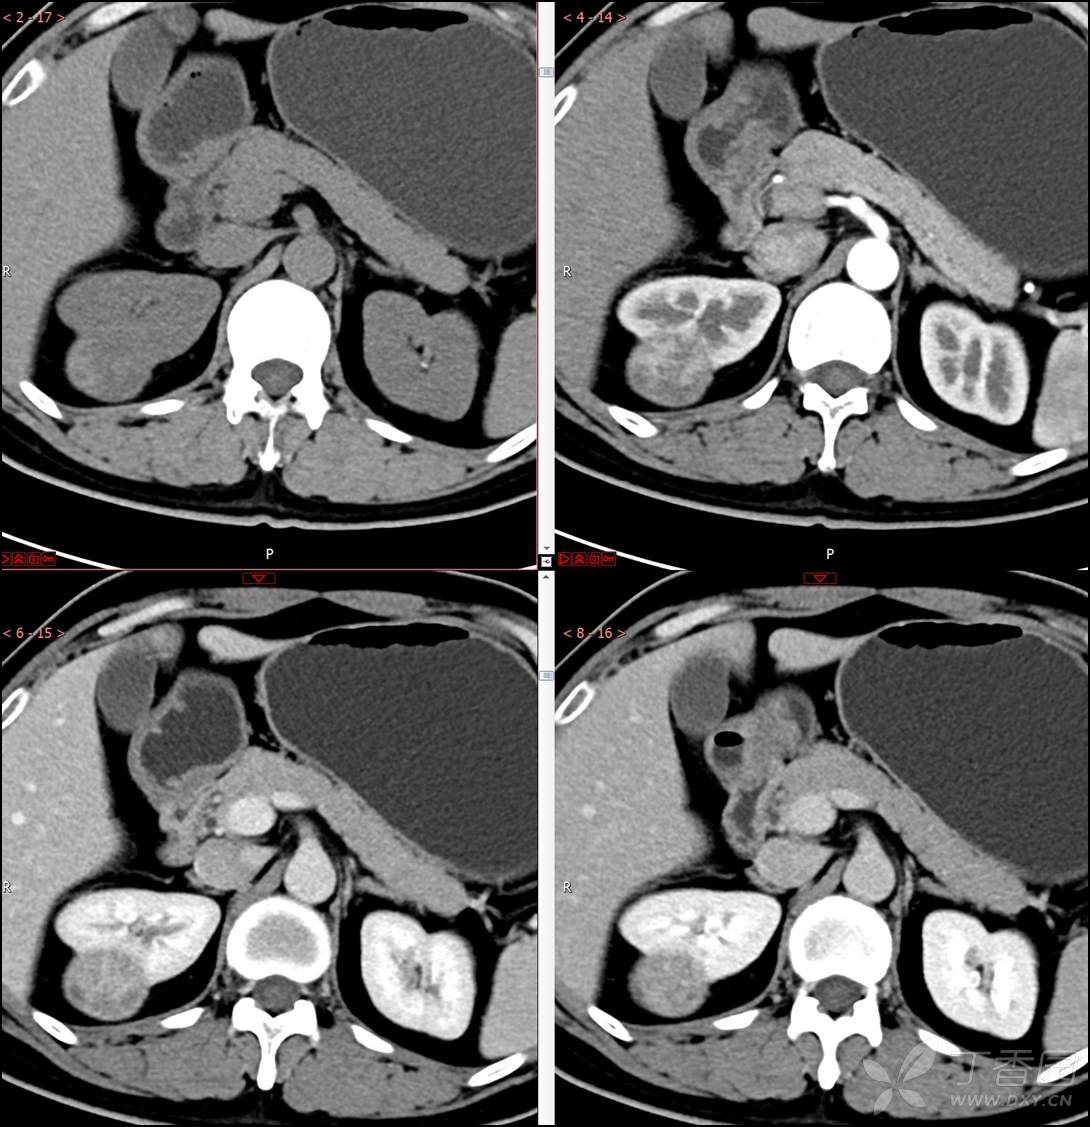

【影诊笔记518】中年男性,查体发现肾脏占位~『回复即可显示答案』

患者年龄:40岁

主诉:查体发现右肾肿物2月余

简要病史:患者2月余前于我院行健康查体,胸部(肺)CT平扫示:右肺中叶结节并右侧阻塞性肺炎;左肺上叶小结节;右肾占位。自诉无腰背部疼痛不适,无尿频、尿急、尿痛,无肉眼血尿,无恶心呕吐,无心悸、胸闷,无发热、寒战等不适,建议进一步检查。现患者为求进一步诊治于为我院就诊,建议手术治疗,门诊遂以“肾肿物(右)”收入院。患者自发病以来神志清,精神可,饮食可,睡眠欠佳,大便正常,体重近期无明显增减。